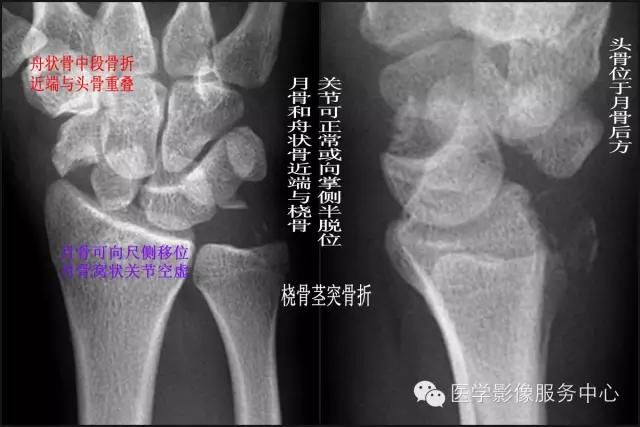

五、经茎突和舟状骨的月骨周围脱位 【受伤机制】 跌倒时手掌着地,腕过度背伸。 【诊断要点】

①尺、桡骨茎突骨折;

②舟状骨中段骨折,近端与头骨重叠;

③月骨可向尺侧移位,月骨窝状关节空虚;

④头骨位于月骨后方;

⑤月骨和舟状骨近端与桡骨关节可正常或向掌侧半脱位。